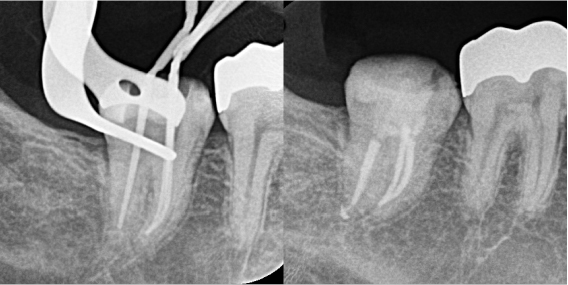

根管治療2回目

2回目の来院時にはほとんど痛みは消失していました。再度根の中を清掃し、根管充填・コア築造まで行い、治療は完了しました。

| 根管洗浄 | 次亜塩素酸ナトリウム溶液・EDTA溶液 |

| 根管貼薬 | 水酸化カルシウム |

| 拡大号数 | MB根#40/04 ML根#40/04 D根#40/02 |

| 根管充填 | バイオセラミックシーラーを用いたHydraulic condensation technique |